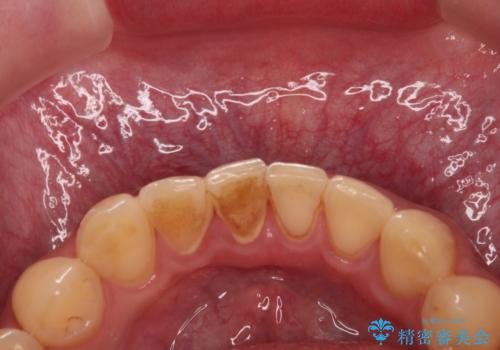

- 茶渋がついて歯の汚れが気になり、きれいにしたいと希望されました。

PMTC(30分コース) 担当衛生士 進藤

着色だけでなく、歯の汚れもとれてツルツルになり気持ちがいいと

喜んでいただけました。